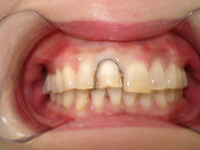

1. 全瓷貼面

應(yīng)用樹脂粘結(jié)劑將薄層全瓷貼面修復體固定于患牙唇面,以遮蓋前牙唇面的變色、缺損。全瓷貼面顏色穩(wěn)定、美觀,不易著色,耐磨損、不易脫落,而且較全冠的磨牙量明顯減少。

修復前

制備后

修復后